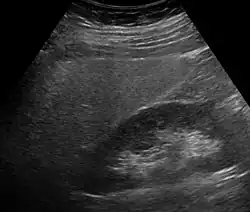

Ultrasound showing diffuse increased echogenicity of the liver

Imaging studies are often obtained during the evaluation process. Ultrasonography reveals a "bright" liver with increased echogenicity. Pocket-sized ultrasound devices might be used as point-of-care screening tools to diagnose liver steatosis.[30] Medical imaging can aid in diagnosis of fatty liver; fatty livers have lower density than spleens on computed tomography (CT), and fat appears bright in T1-weighted magnetic resonance images (MRIs). Magnetic resonance elastography, a variant of magnetic resonance imaging, is investigated as a non-invasive method to diagnose fibrosis progression.[31]